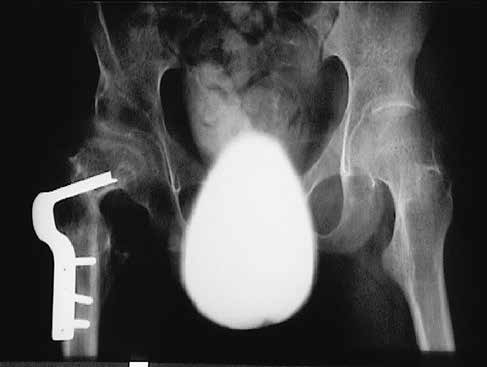

Rekonstruktiver Hüfteingriff

Der rekonstruktive Hüfteingriff mit offener Reposition ist nach Erfahrung internationaler und auch unseres Zentrums bei Hüftluxationen Erwachsener gegenüber anderen Verfahren wie Resektionen zu bevorzugen (Abb. 5 u. 6).Frühere Mobilisierung ohne Gipslagerung brachte in den vergangenen Jahren einen großen Vorteil für die betroffenen Kinder und ihre Familien.

Postoperativ sind eine frühe Mobilisierung, eine symmetrische Lagerung im Sitzen und Liegen sowie eine langsam beginnende regelmäßige Steh- und Gehtherapie mit neuen Bewegungstrainern anzustreben.